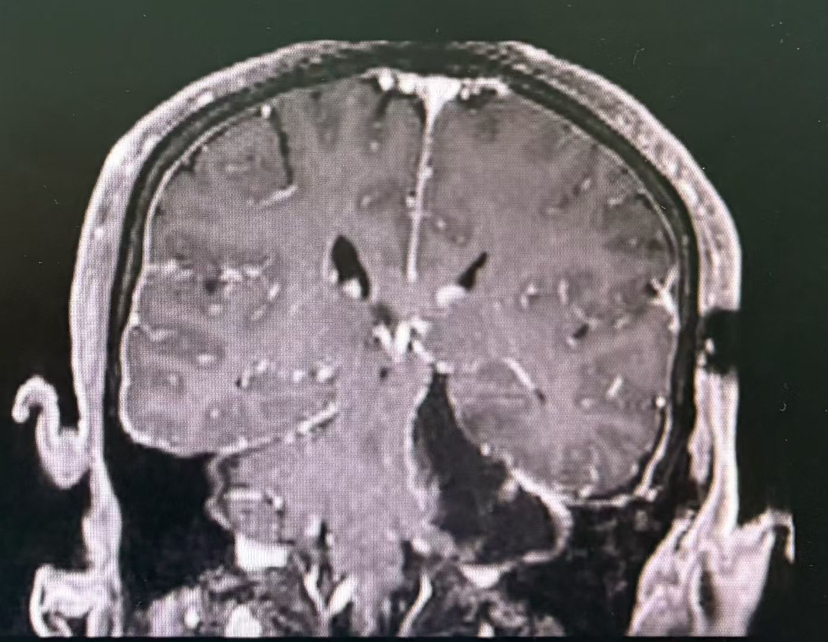

术前MRI

术后MRI